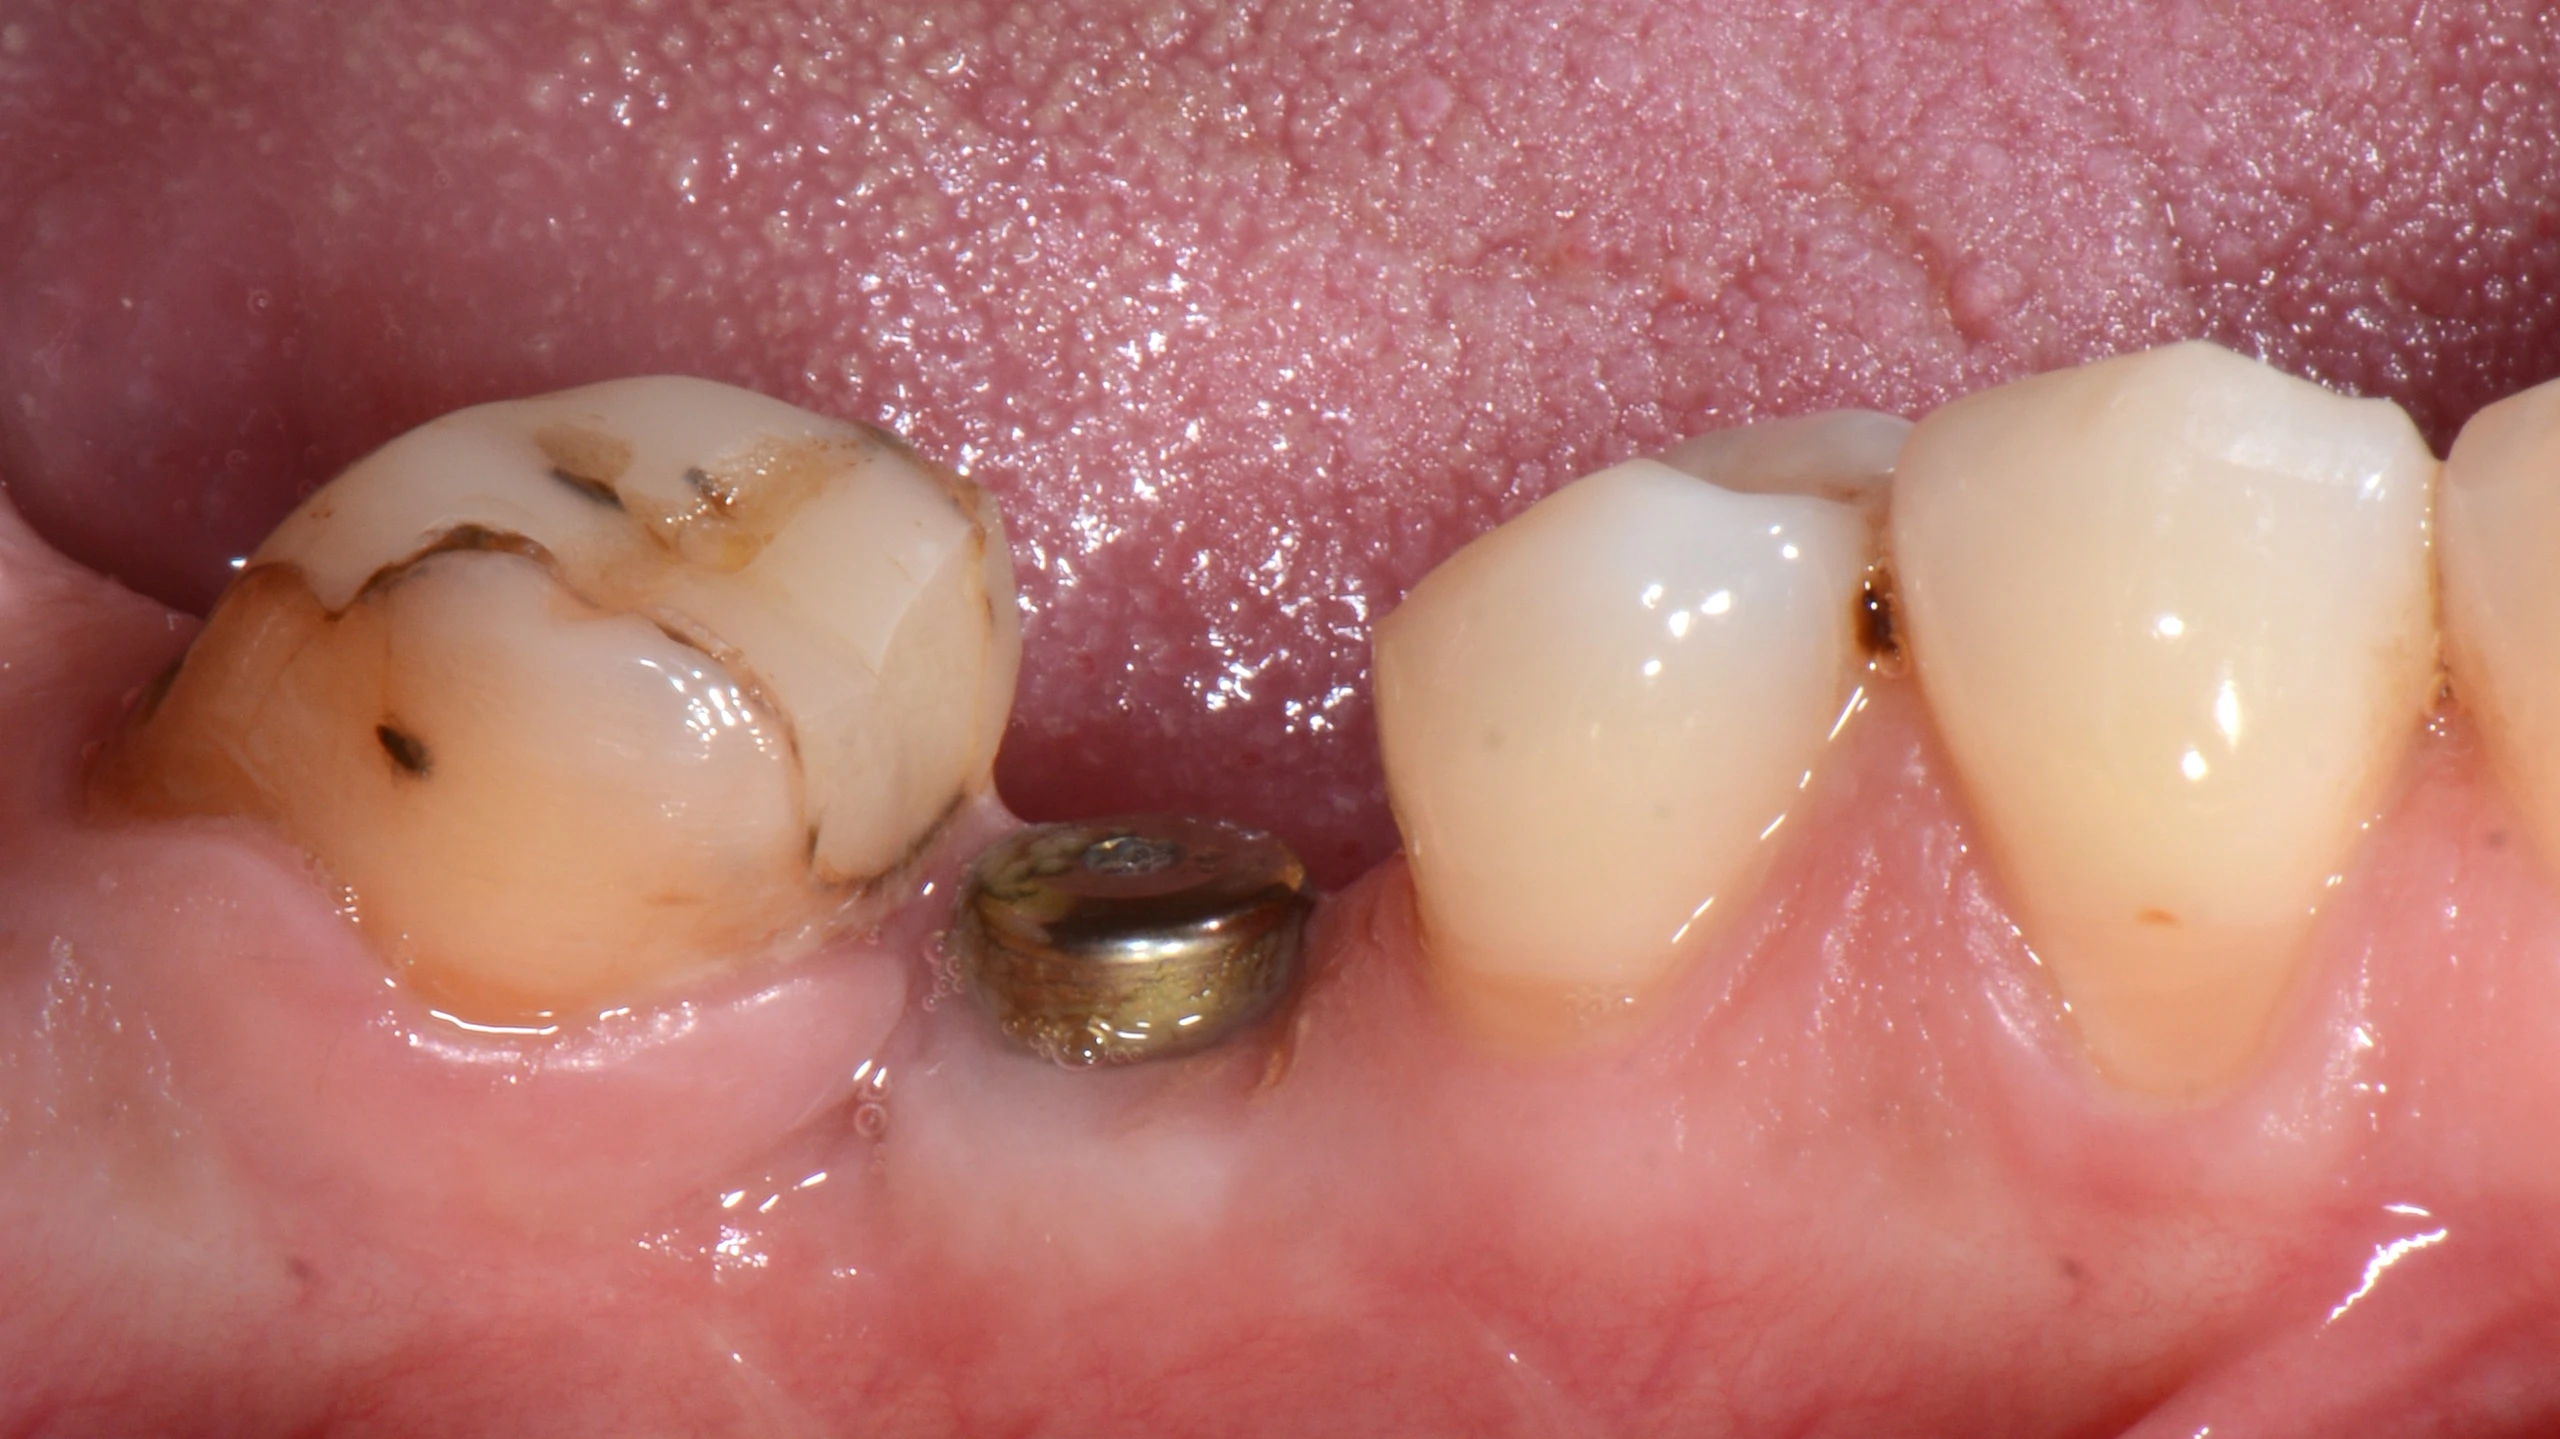

В данном кейсе не стали прибегать к ортодонтическому лечению, а просто установили имплантат MIS С1